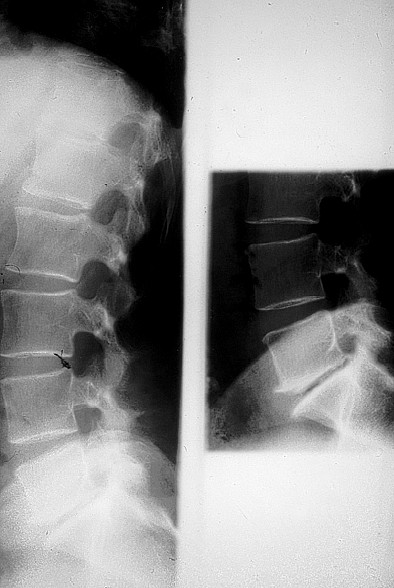

Les images de spondylite sont constituées par des érosions des angles vertébraux, cernées par une réaction osseuse condensante (spondylite érosive de Romanus), rendant le bord vertébral antérieur rectiligne (mise au carré des vertèbres). Secondairement, se développe un processus d’ossification sous-ligamentaire à partir des angles vertébraux : c’est le syndesmophyte (plus fin et plus vertical que l’ostéophyte) pouvant conduire à une ossification intersomatique (colonne « bambou » des spondylarthropathies) (figure 1.3).

Fig. 1.3. Aspect radiographique de spondylarthropathie inflammatoire chronique. Atteinte caractéristique de la charnière dorsolombaire avec, à la phase de reconstruction, une ossification en « pont » dénommée syndesmophyte